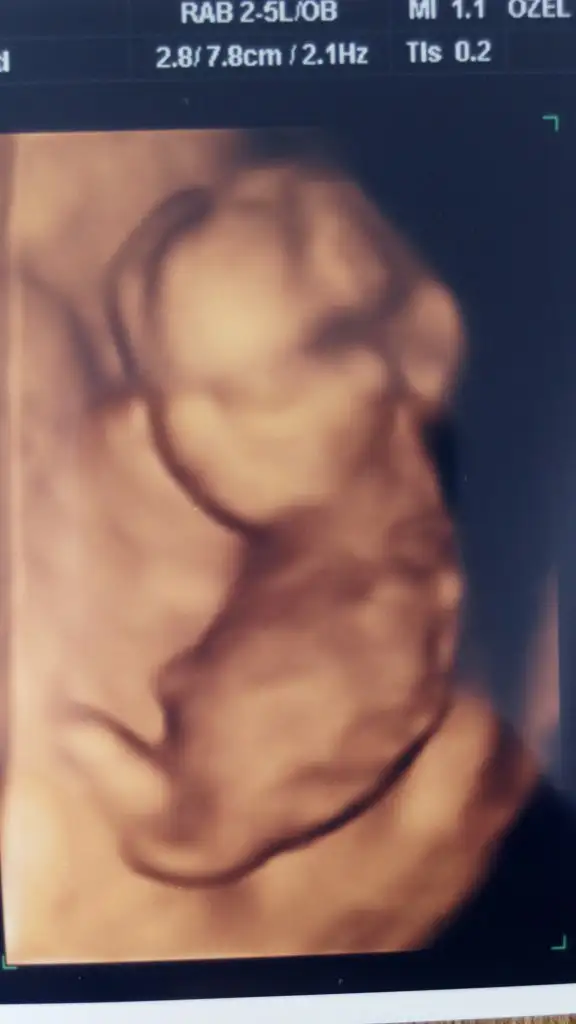

Sizinki de erkeğe benziyor ama çok iyi göremedim sağlıkla hayırla gönlünüze göre olsun inşAllah

Bnada yorum yapar Muş’un cnmErkek büyük ihtimal canım

Erkek gibi geldi canimmBnada yorum yapar Muş’un cnm